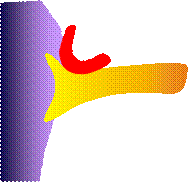

Prinzip der mikrovaskulären Dekompression

Deutlicher Kontakt zwischen

N. Trigeminus und einem Blutgefäß

(A. cerebelli superior)